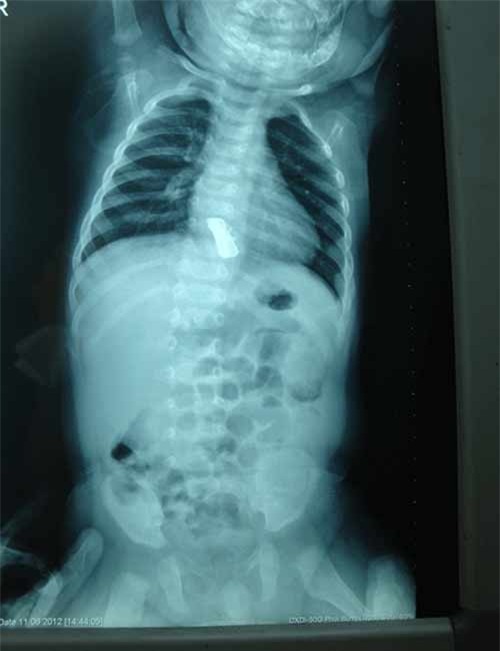

Ông được gia đình đưa tới khám tại bệnh viện Việt Nam – Thụy Điển Uông Bí, Quảng Ninh. Sau khi tiến hành thăm khám lâm sàng và xác định bằng nội soi phế quản bằng ống soi mềm các bác sĩ phát hiện 1 dị vật bít gần hết phế quản phân thùy 9.

Dị vật đã gây sùi lòng phế quản, nhiễm trùng trong lòng phế quản. Người bệnh được chỉ định nội soi ống cứng gắp dị vật. Dị vật được lấy ra khỏi phế quản của người bệnh là một mảnh xương cá kích thước 12x10x8mm.

X quang thực quản cổ nghiêng có dị vật đoạn C3-C4. Soi hạ họng - thanh quản: Thấy miệng nhiều máu bầm ứ đọng, hút sạch kiểm tra thấy có vết thủng thành sau họng tại điểm 7 giờ vùng hạ họng, phía trên miệng thực quản 2-3 cm.